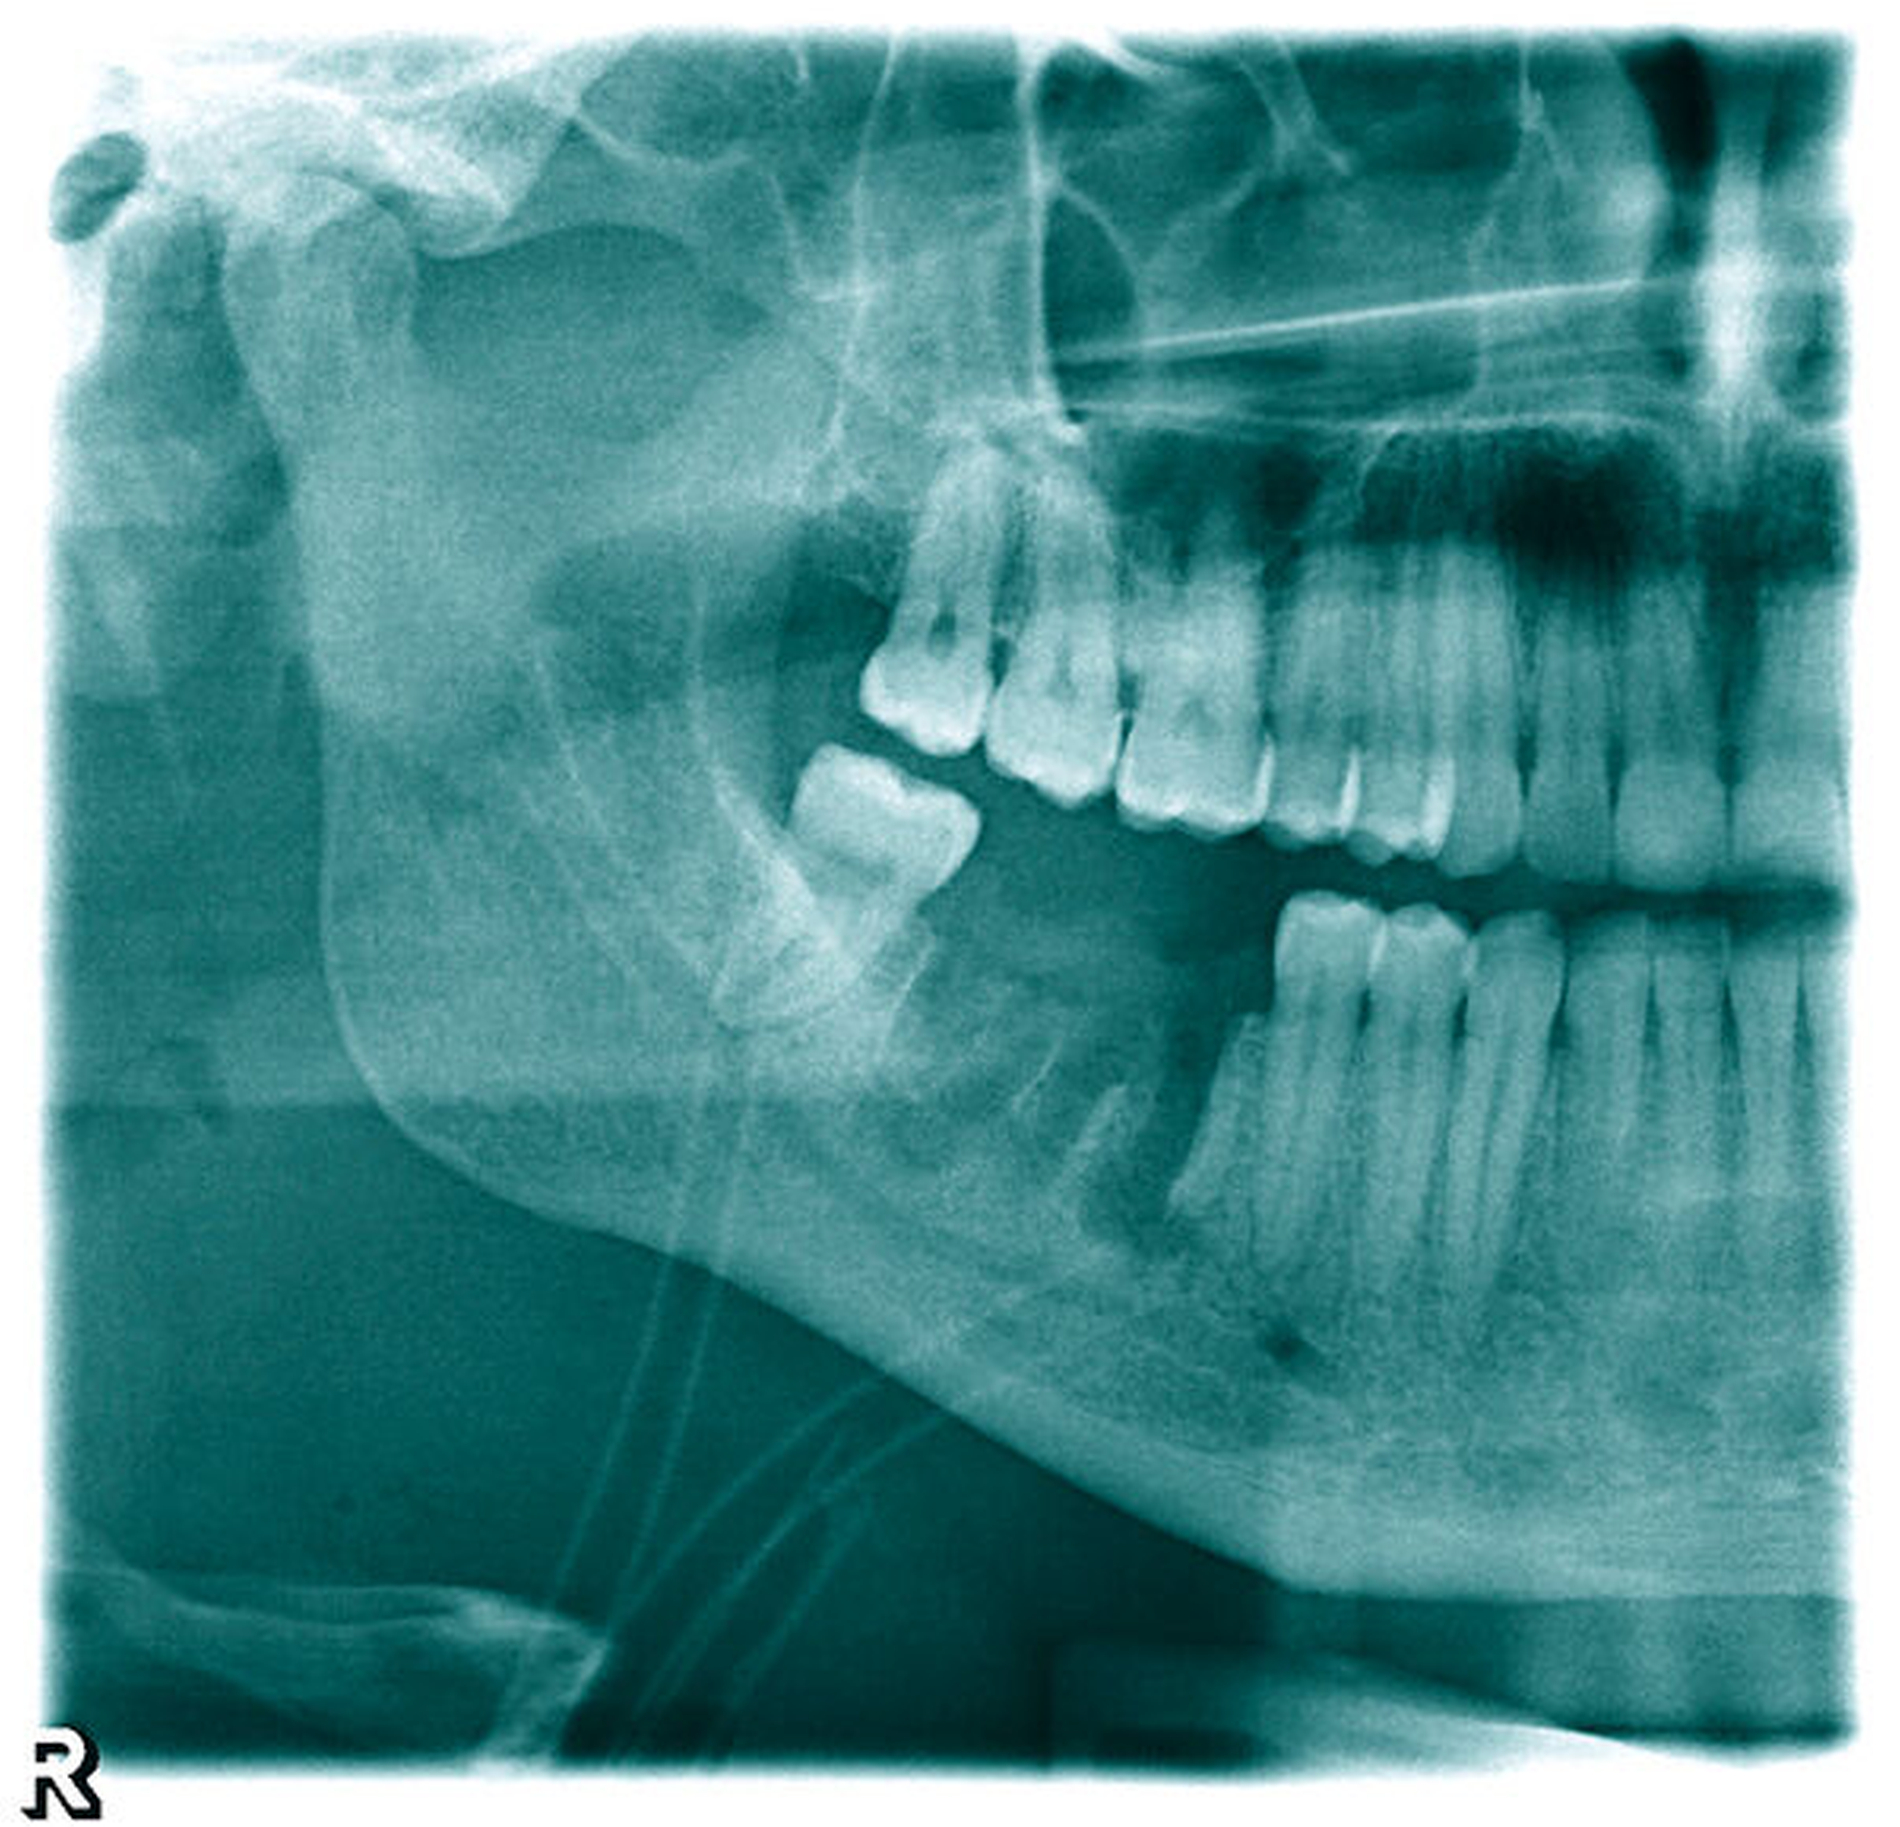

Die postoperative Bildgebung (Halbseiten-OPTG) zeigt die Extraktionsalveolen 46 und 47 ohne Anhalt auf Wurzel- oder Materialreste ebenso wie die eingelegten Drainageröhrchen (Abbildung 2). Während des postoperativen Heilungsverlaufs war die Schwellung nur langsam regredient und der Abgang putriden Sekrets über die extraorale Wunde weiterhin stark, so dass eine Computertomografie (CT) des Halses zum Ausschluss eines Wurzelrests, einer Fraktur oder einer Ausbreitung durchgeführt wurde. In dieser fielen nebenbefundlich circa 10 mm messende Verdichtungen in beiden Lungenoberlappen im Sinne punktuell verkalkter Kavernen auf (Abbildung 3).